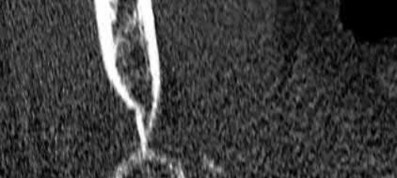

Illustration A shows a heterotrophic non-union of the tibia after intramedullary nailing. The patient was treated with exchange nailing with a larger nail. On the right shows a 4 month post-op radiograph after exchange nailing showing osseous union at the fracture site.